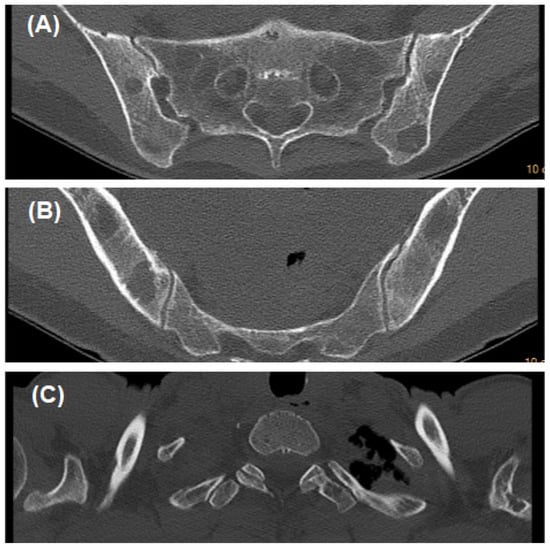

2. Case Description